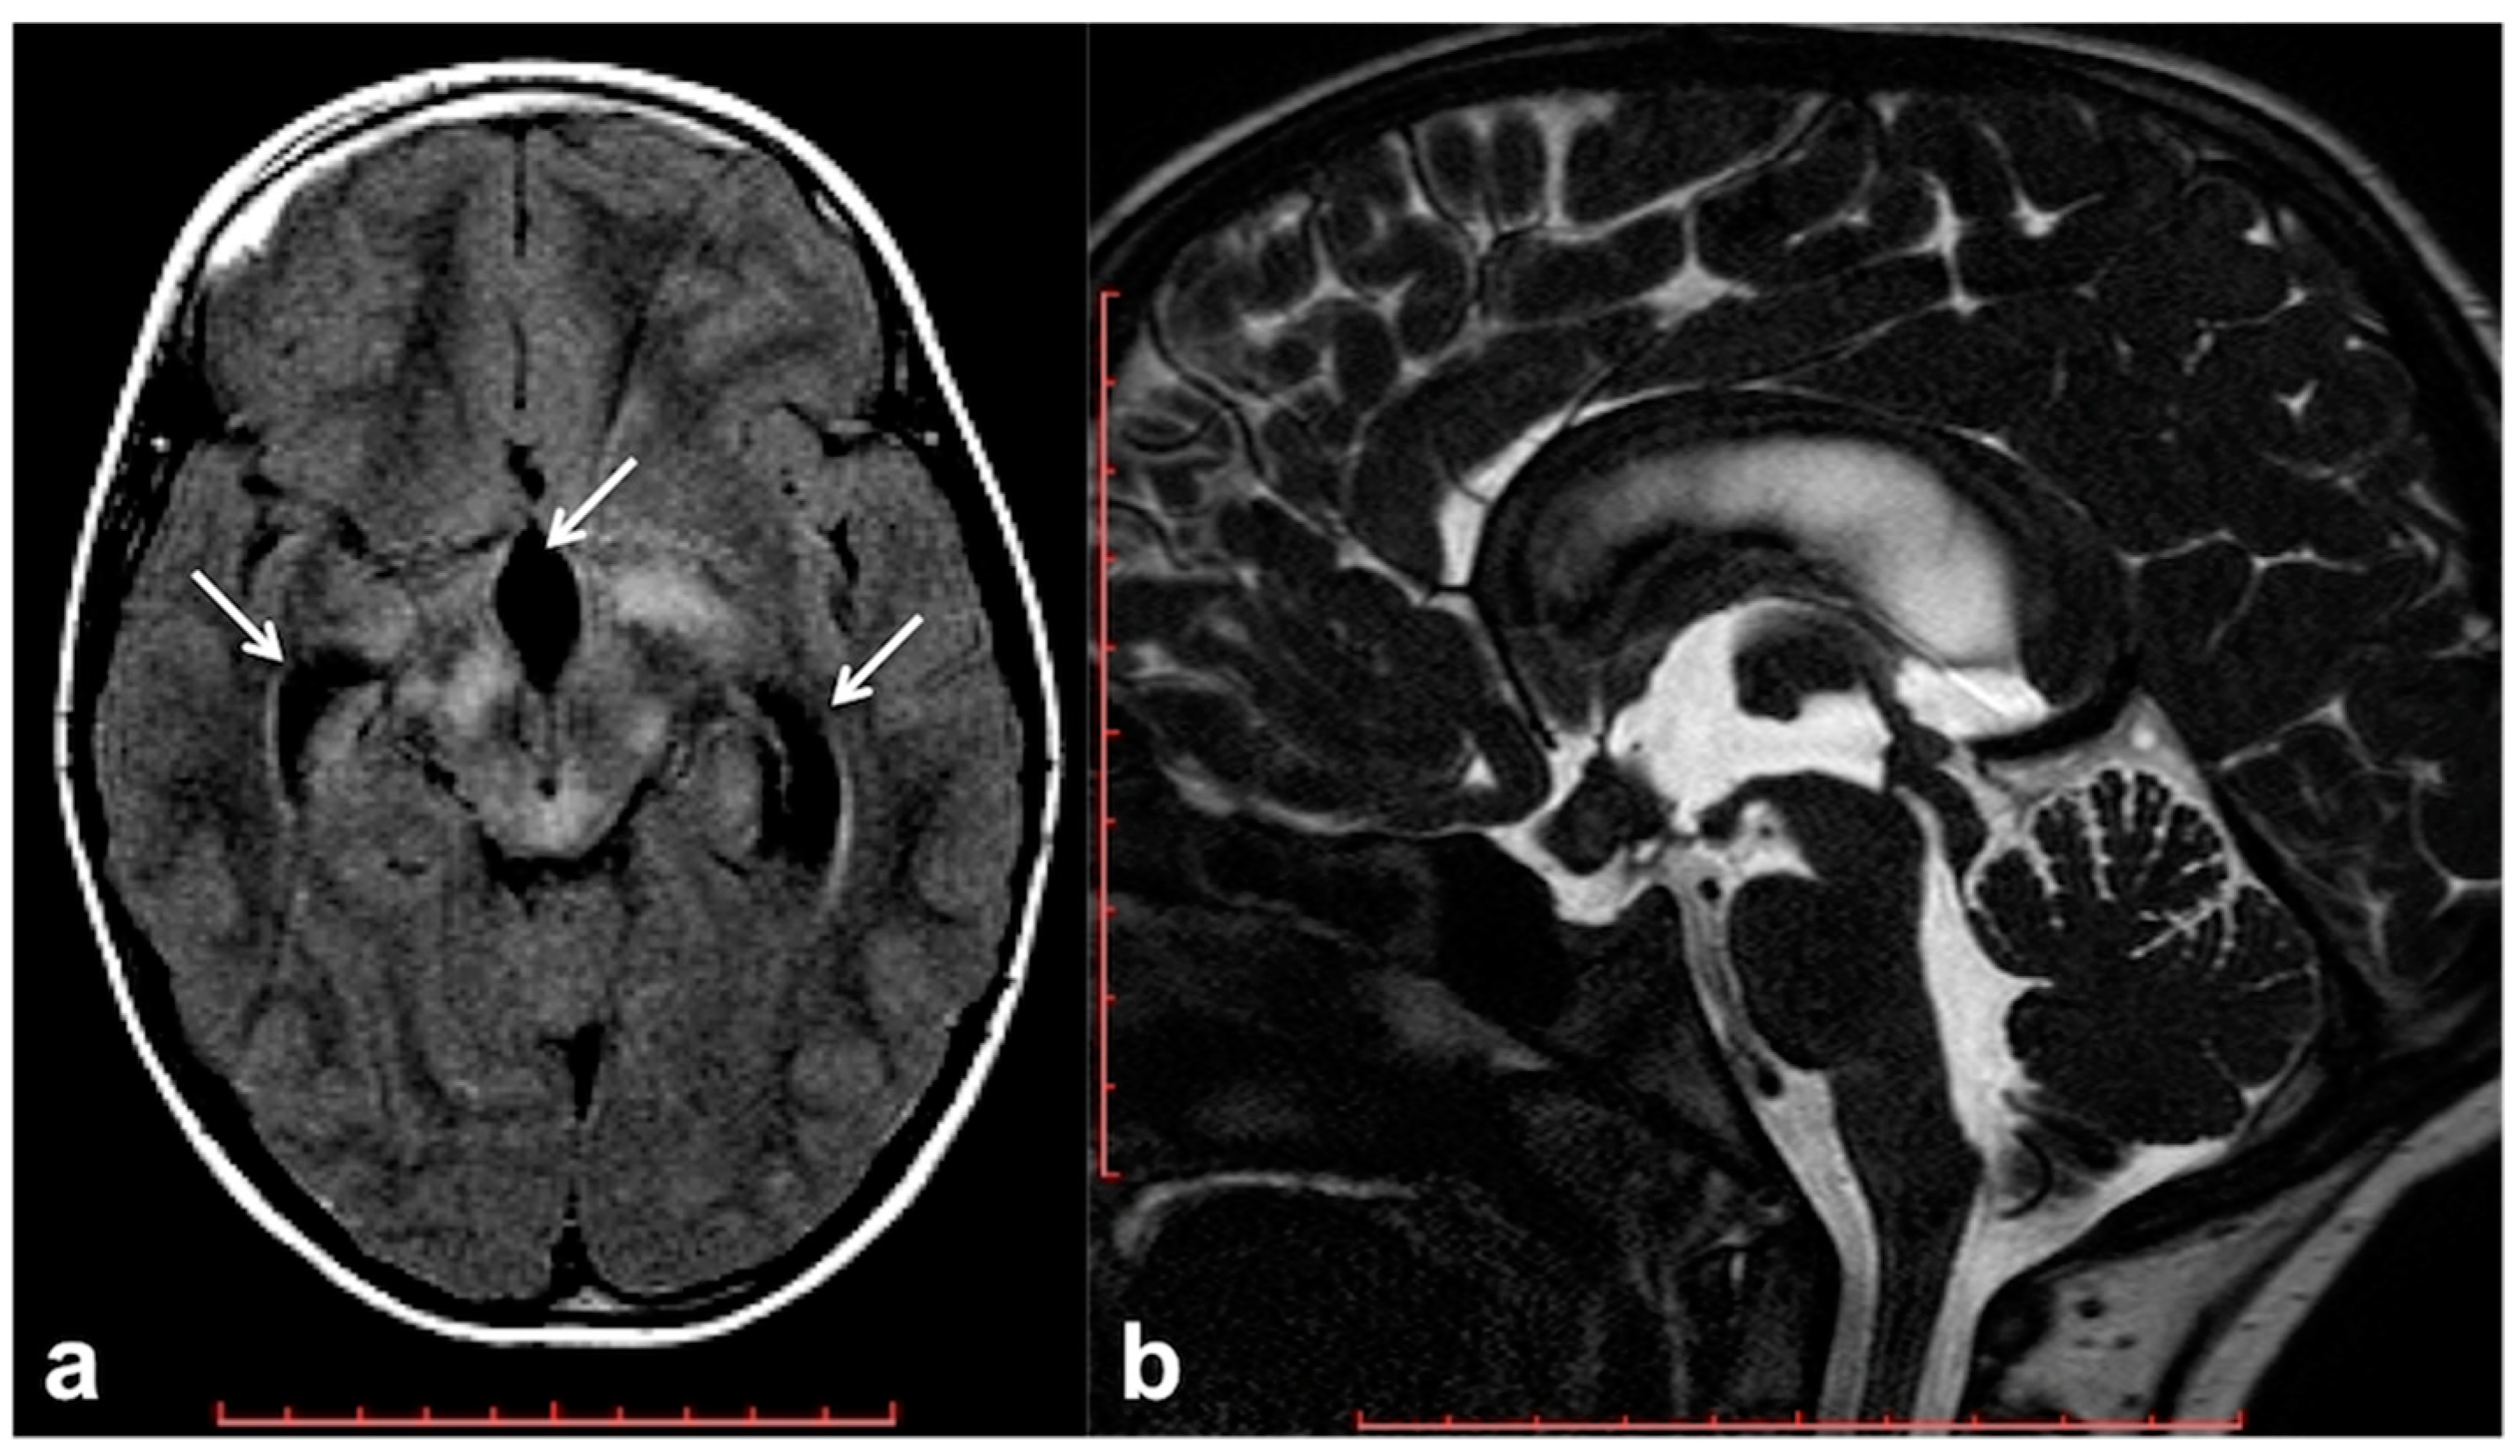

2.4. Altered Cerebrospinal Fluid Dynamics: Obstructive Hydrocephalus Other Than Tumor-Related

- Roth, J.; Constantini, S.; Cinalli, G. Neurofibromatosis type 1–related hydrocephalus: Causes and treatment considerations. Child’s Nerv. Syst. 2020, 36, 2385–2390. [Google Scholar] [CrossRef]

- Sill Kang, Y.; Park, E.; Kim, Y.; Kim, J.; Kim, D.; Thomale, U.W.; Shim, K.W. Altered cerebrospinal fluid dynamics in neurofibromatosis type l: Severe arachnoid thickening in patients with neurofibromatosis type 1 may cause abnormal CSF dynamic. Childs Nerv. Syst. 2017, 33, 767–775. [Google Scholar] [CrossRef] [PubMed]

- Glombova, M.; Petrak, B.; Lisy, J.; Zamecnik, J.; Sumerauer, D.; Liby, P. Brain gliomas, hydrocephalus and idiopathic aqueduct stenosis in children with neurofibromatosis type 1. Brain Dev. 2019, 41, 678–690. [Google Scholar] [CrossRef]

- Roth, J.; Ber, R.; Wisoff, J.H.; Hidalgo, E.T.; Limbrick, D.D.; Berger, D.S.; Thomale, U.W.; Schulz, M.; Cinalli, G.; Santoro, C.; et al. Endoscopic Third Ventriculostomy in Patients with Neurofibromatosis Type 1: A Multicenter International Experience. World Neurosurg. 2017, 107, 623–629. [Google Scholar] [CrossRef]